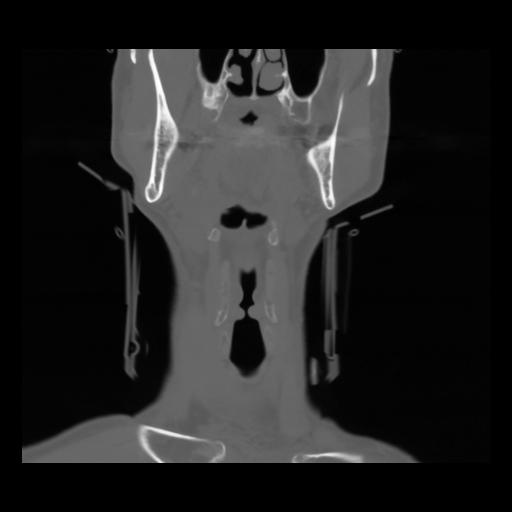

13 P.BLANDAS,,Coronal,2.000,P.BLANDAS,Coronal,